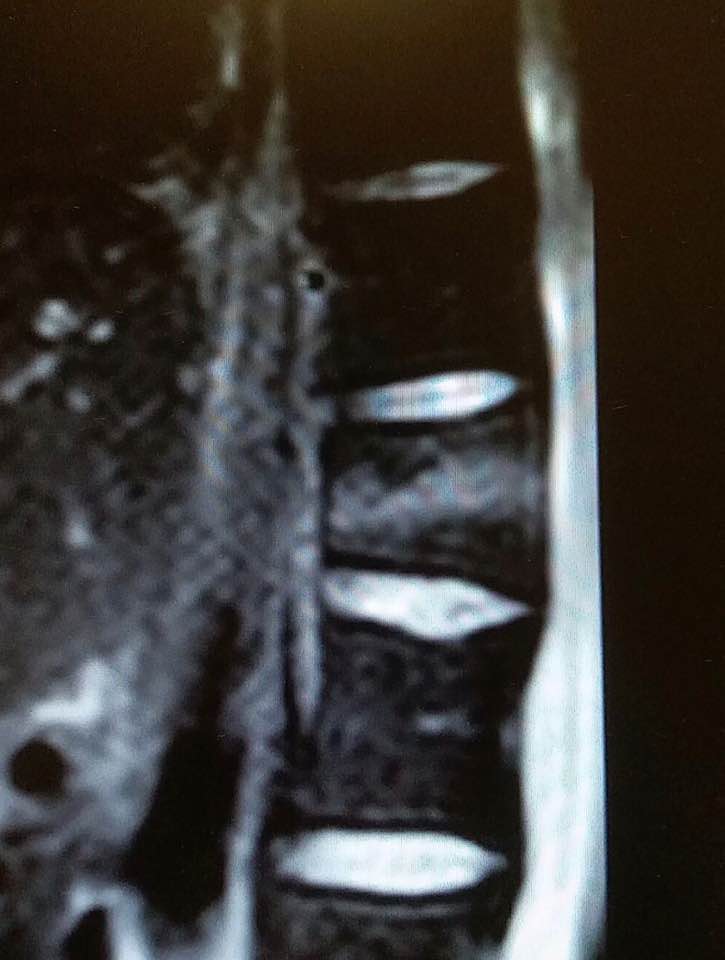

嚴重的工業意外受傷,T12胸脊椎不穩定的3段(前、中、後柱列)壓迫性脊柱椎體骨折

1. 即使您的胸部及胸脊椎柱被8英尺高和200磅重的巨大雪櫃嚴重壓碎, 您仍然生存, 您的中樞脊髓神經但沒有受到傷害.

3. 幸運的是,入院前及兩天來你未有因為不穩定的脊柱椎體骨折碎片的移位而導致你脊髓中樞神經到不可逆轉和永久性的損傷致雙腿癱瘓及大小便失禁. 今天所有穩定你碎裂脊椎的手術都做完了.